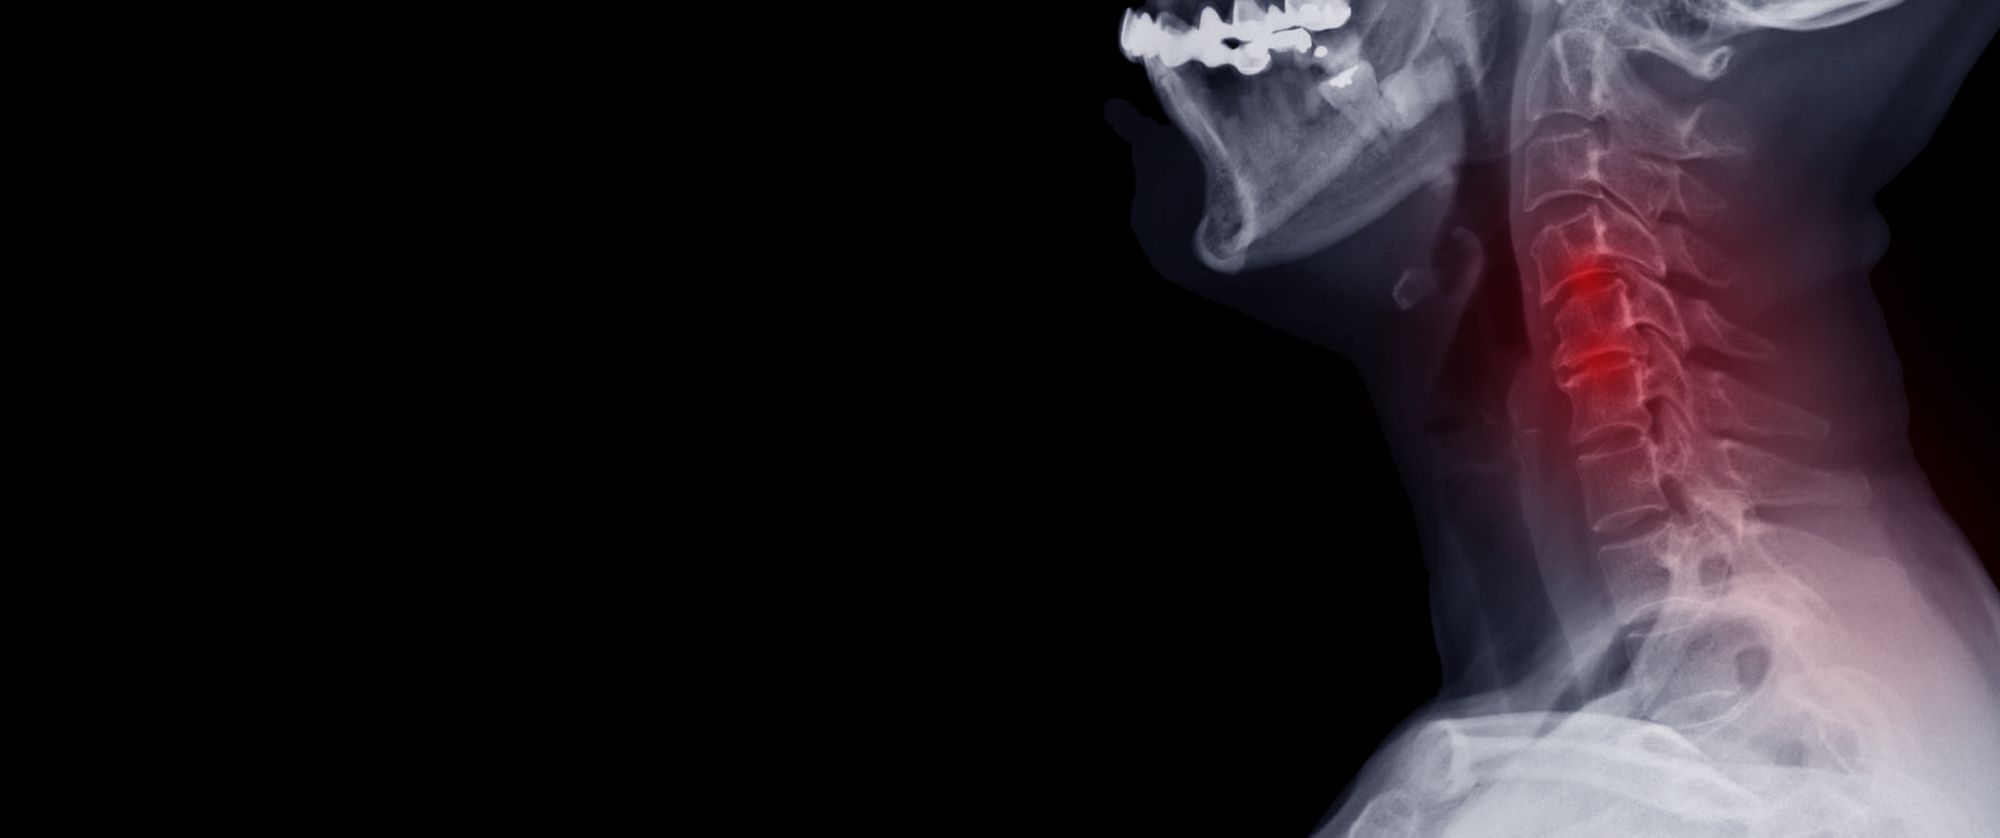

Cervical spondylosis with Myelopathy

The spinal cord is subjected to various changes as an individual starts growing old. These changes alter the shape and structure of the spine and its adjacent structures. Cervical spondylosis with myelopathyis a condition that is concerned with nerves which gradually gives rise to painful neck conditionsdue to changes in the spinal cord and the other structures around it. It has become a prevalent occurrence among adults yet in most cases there seems to be delays in its diagnosis and treatment.

The spinal cord is a pathway through which impulses are transmitted from the brain to different parts of the body. Hence, damage or changes in the spine has a high chance of causing numerous problems all over the body. Cervical spondylosis with myelopathy gives rise to pain and stiffness in the neck because of compression of the cords. However, the signs of occurrence may not always be prominent. But when there is a hindrance in the flow of impulses due to the narrowing of the cords, the following symptoms can be felt-